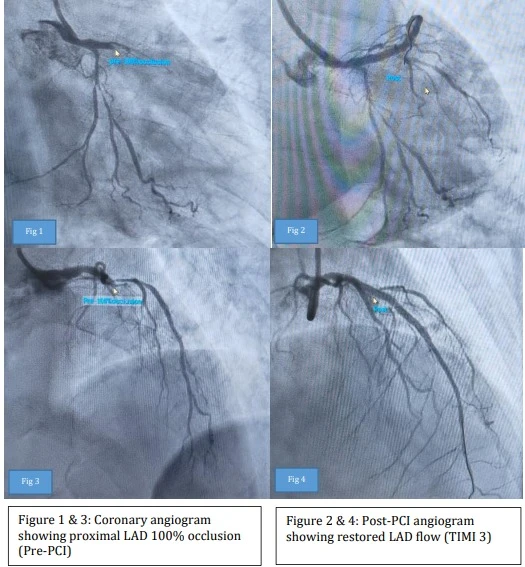

05th Nov 2025 | Medicover Hospitals | NashikA patient suffering from hemophilia was admitted to Ashoka Medicover Hospital, Nashik, with severe chest pain and difficulty in breathing. On examination, the patient was diagnosed with a major heart attack. Angiography revealed that a major blood vessel in the heart was 95% blocked. Considering this situation, primary angioplasty was a must. But since the patient had hemophilia, the risk of bleeding during the procedure was very high.

With careful planning and close coordination between the teams, the angiography and primary angioplasty were successfully performed. There was no bleeding during the treatment, and the patient made a complete recovery.